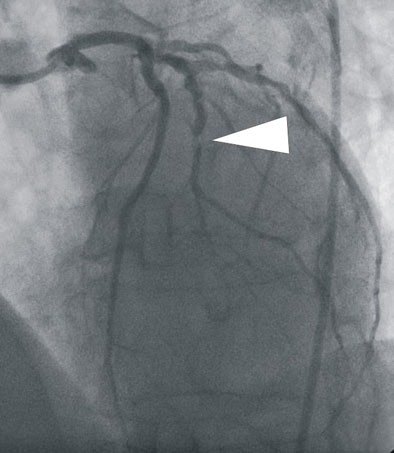

| In a 64-year-old man presenting with chest pain, 3D and multiplanar reconstructions of coronary CTA images show a significant stenosis in the first diagonal branch of the left anterior descending (LAD) artery and a 70% stenosis in the mid right circumflex artery (RCA) (arrows). All images courtesy of Dr. Balázs Ruzsics, Ph.D., and Dr. U. Joseph Schoepf. |

| In a 64-year-old man with chest pain, conventional catheter angiography confirmed the coronary CTA findings, and described a 50% ostial stenosis with diffuse disease throughout the vessel and a discrete 90% stenosis in the mid right circumflex artery (RCA) (arrows). |